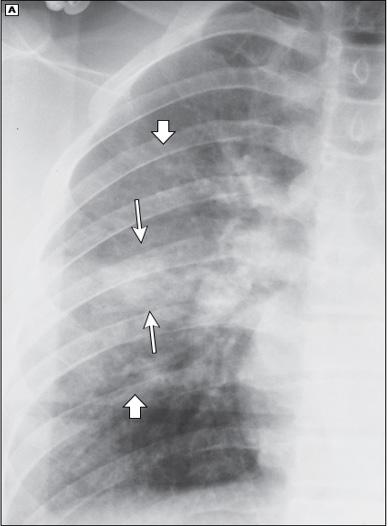

Figura 9. Hemotórax por acumulo de sangre en espacio pleural por laceración pulmonar Figura 10. Hemotórax → aumento de radiopacidad en hemitórax izquierdo Figura 11. La radiografía de tórax en posición vertical muestra una combinación de hemoneumotórax (flechas gruesas y delgadas, respectivamente). Figura 12. TAC tórax → ↑sensibilidad y especificidad para diagnóstico de hemotórax como se muestra en la imagen en lado izquierdo